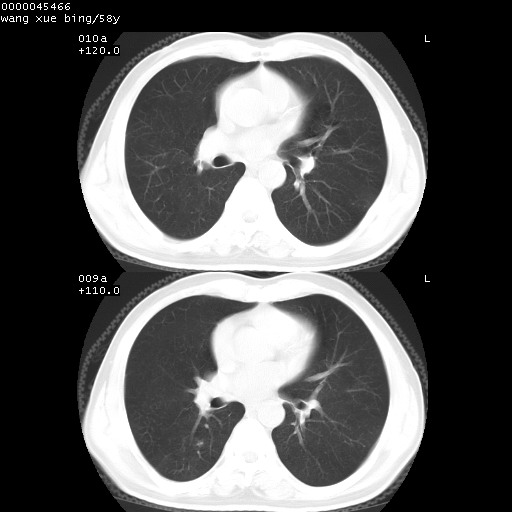

患者 男,58岁。咳嗽、咯血3月余。

胸部cr x线片提示:1)右下肺脓肿。2)右下肺周围型肺癌不排除。建议:行ct扫描检查。

胸部ct轴位平扫(层厚10mm,螺距1.5,重建间隔10mm),图像如下:

右肺下叶团块及不规则空洞,内壁不规则,外缘见粗长毛刺,临近胸膜明显增厚并与病灶关系密切。支持考虑:右肺肺脓肿!建议穿刺病理检查待除外周围型肺癌!

右肺下叶见不规则厚壁空洞,内壁不规则,外缘见粗长毛刺,临近胸膜明显增厚并与病灶关系密切。支持考虑:周围型肺癌!

右肺下叶周围型肺癌伴空洞形成!征象比较明显!分叶、毛刺、胸膜凹陷征、厚壁空洞,壁结节!

空洞壁厚,不规则,其内可见壁结节,周围可见毛刺及阻塞性炎变,多考虑癌性病变.